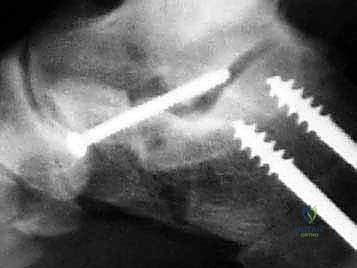

في هذا الدليل المرجعي، سنسلط الضوء بشكل مكثف على الحل الجراحي المتقدم والفعال المعروف باسم إطالة العمود الجانبي للقدم (Lateral Column Lengthening)، وتحديداً التقنية الجراحية الدقيقة المسماة "قطع عظم إيفانز" (Evans Osteotomy). يُعد هذا الإجراء حجر الزاوية في استعادة الميكانيكا الحيوية الطبيعية للقدم، وإعادة بناء القوس المنهار، وتخفيف الألم بشكل دائم.

التصوير الشعاعي:

* الأشعة السينية (X-rays) مع تحمل الوزن: ضرورية لتقييم درجة انهيار القوس وزوايا العظام (مثل زاوية تالونافيكولار Meary's Angle).

* الأشعة المقطعية (CT Scan): في الحالات المعقدة أو عند التخطيط الجراحي الدقيق لتقييم جودة العظام ووجود أي التهاب مفاصل خفي.